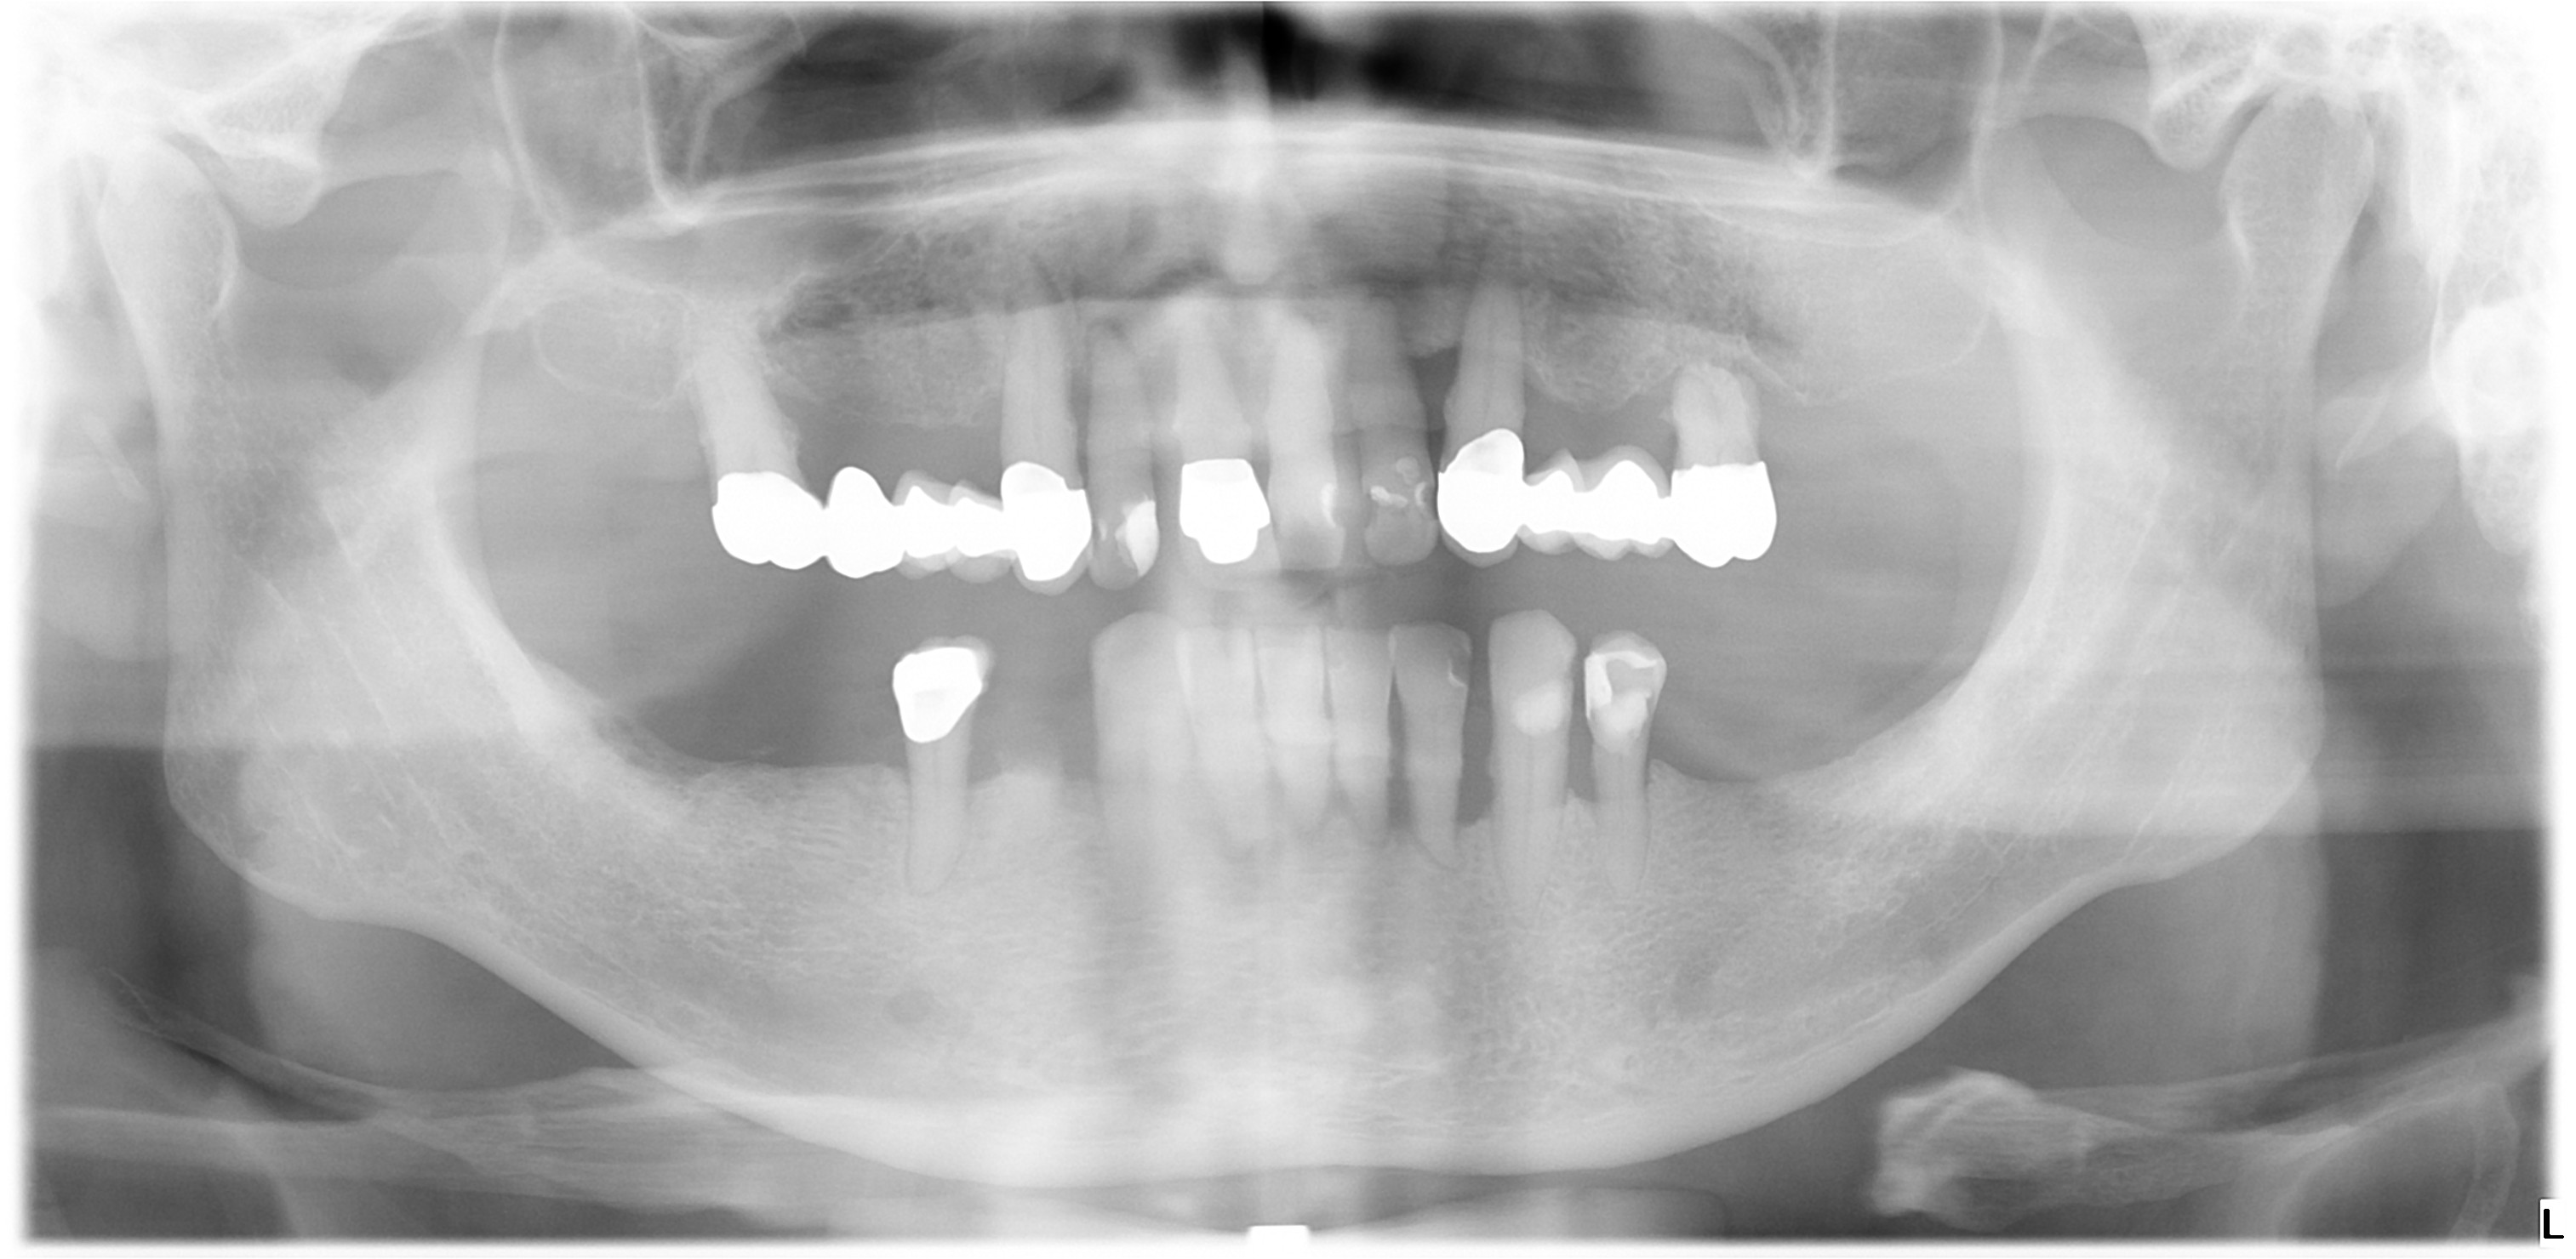

12 Implantate setzen mit Sinuslift, Knochenaufbau und festsitzender Versorgung (Narkose)

I. Befund des gesamten Gebisses / Behandlungsplan

Oberkiefer

11 BM x x BM 21

12 SKM x x SKM 22

13 BM x x BM 23

14 SKM b b SKM 24

15 BM b b BM 25

16 SKM b x SKM 26

17 x f 27

18 f f 28

Unterkiefer

48 f f 38

47 f f 37

46 SKM f f SKM 36

45 BM x f BM 35

44 SKM x x SKM 34

43 BM x x BM 33

42 SKM x x SKM 32

41 BM x x BM 31